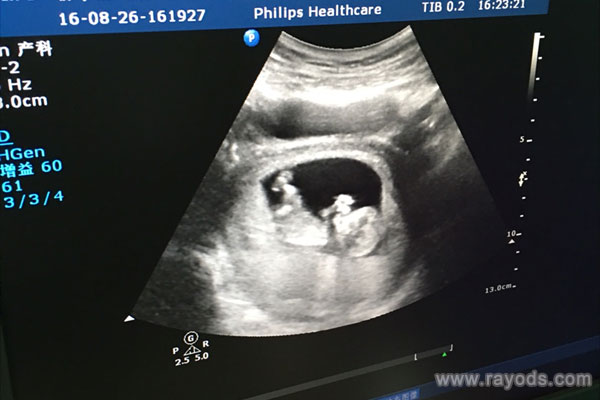

NT哪三个亮点能看出来是男孩女孩? 网传通过NT检查可以看到胎儿的性别特征和生殖器特点,腿间亮点和白线就是重要判断依据,如果看到胎儿双腿间有三个亮点的话可大致判断为..

随着科学技术的不断发展,孕检在早期就能揭开胎儿性别的神秘面纱,其中NT指的是颈背部透明带厚度。而在孕检过程中,有三个亮点可以帮助准父母区分胎儿的性别。那么孕检中NT..

很多准妈妈怀孕后好奇怀的是女孩还是男孩?听说NT上有3个亮点的,多数是男宝宝。这种说法是真的吗?生殖专家说:这种说法不靠谱。网传:根据nt结果看胎儿性别的方法双腿间..

很多准爸爸准妈妈不是重男轻女,而只是单纯的想知道是男孩还是女孩,以便后续准备宝宝衣服。但我们通过民间办法的话也需要在五六个月肚子稍微隆起才敢根据形态猜测男女。那..